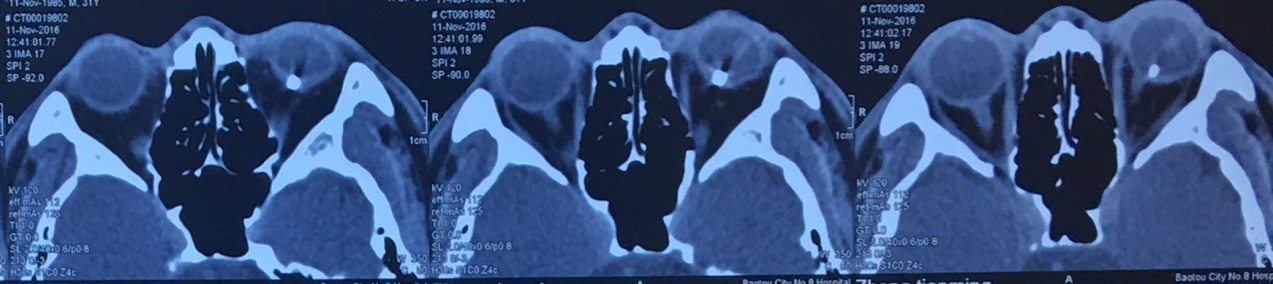

2.阅片记录

2016年11月11日眼眶CT片示:左眼球内异物影,余未见明显异常。

2016年11月11日眼眶CT片